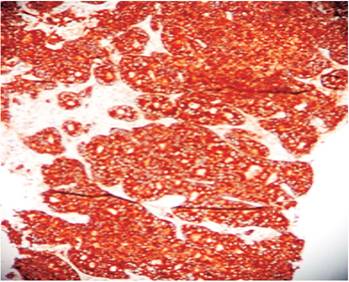

A fine needle aspiration (FNA) biopsy contained low-grade epithelial tumor type adenocarcinoma of possible endocrine origin. A laparoscopic thick trocar biopsy reported the same characteristics as the FNA biopsy (Figures 1 and 2). Computed tomography (CT) of the abdomen, retroperitoneum, thorax and mediastinum showed no abnormalities.

Figure 1 Microphotograph of a liver biopsy showing diffuse metastatic infiltration by malignant cellular nests. H/E-20 X.